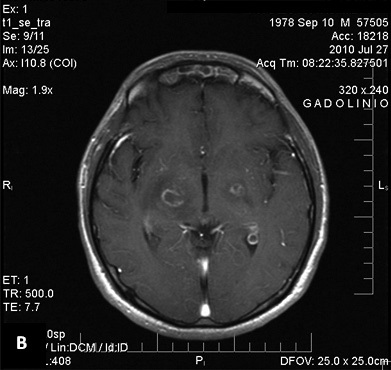

La RM detecta tanto imágenes antiguas como recientes. En T2, pueden dar focos de señales heterogéneas que se confunden con el edema periférico. En T1, se observan zonas hipointensas rodeadas de un halo hipointenso correspondiente al edema periférico (25), que miden entre 1 y 3 cm de diámetro, múltiples en el 85 % de los casos. Captan en anillo la sustancia paramagnética gadolinio. Tienen efecto de masa y se rodean de edema vasogénico, en forma variable. El mayor compromiso es profundo, a nivel de los núcleos basales (75-88 %) y subcortical. El compromiso hemorrágico es raro (25).

En la figura 3, se observa la imagen axial en RM, que muestra compromiso cerebral a base de forma captadora en anillo y rodeado de edema a nivel de los ganglios basales de un paciente inmunodeprimido por VIH/sida.